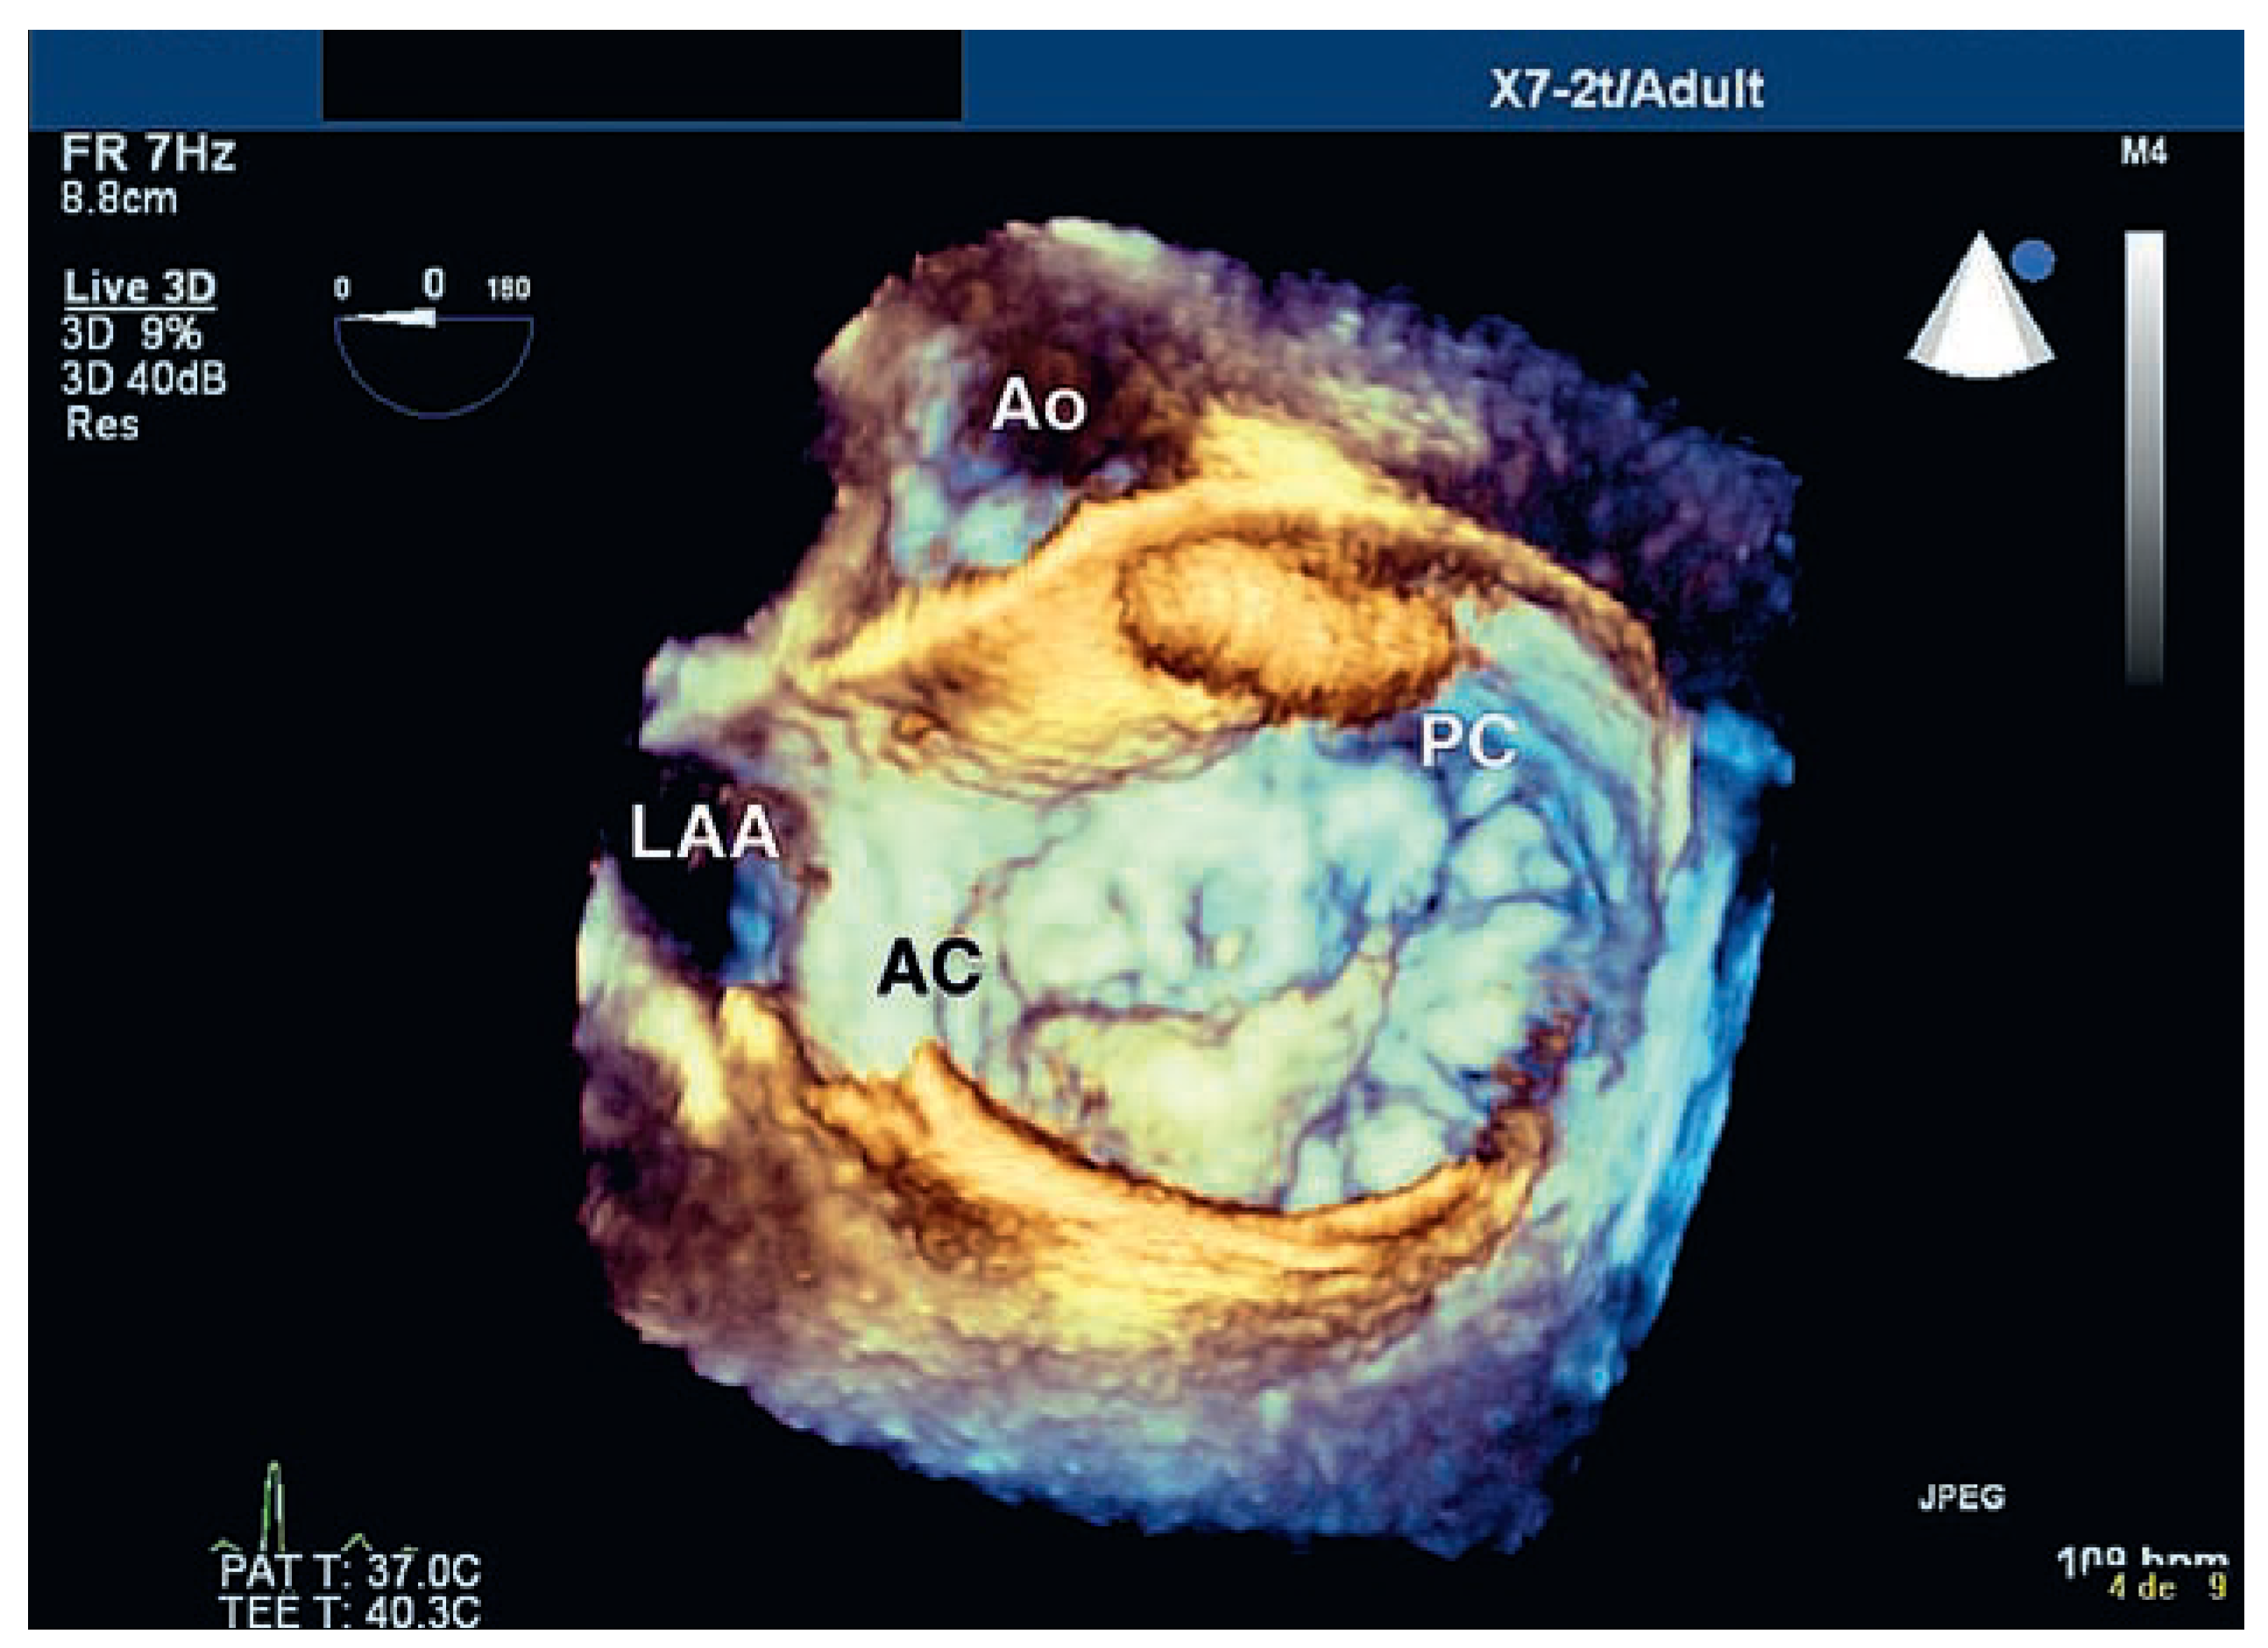

Insuffisance Mitrale: Apport de L’échographie Tridimensionnelle

Case report